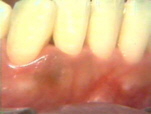

Dos semanas después del

tratamiento la gingiva tiene una apariencia pálida saludable. El paciente ha practicado los procedimientos

eficaces de higiene oral desde el tratamiento. |

Aquí la condición

gingival en lingual es saludable después de un par de semanas del

tratamiento. |

| El lado derecho presenta

la misma condición gingival que el izquierdo. |